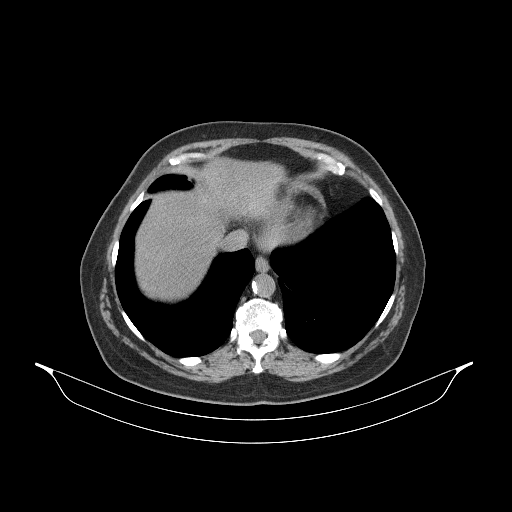

Original VENOUS CT scan

Full window (WL 1023.5, WW 4095 β†’ Low βˆ’1024, High +3071)

Actual HU range: [-160.0, 240.0]